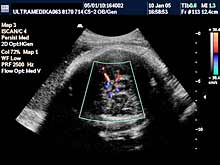

A) Savremena dijagnostika korišćenjem Broad band kolor Dopplera (Broad band-CD) i kolor Power Dopplera (CPD) bez obzira na količinu krvi koja prolazi kroz vaskularnu anomaliju i bez obzira pod kojim uglom je moguće poslati ultrazvučni talas, je u stanju da postavi dijagnozu ove ozbiljne vaskularne malformacije CNS. U nepovoljnim uslovima standardna ultrazvučna tehnika sa CD nije u stanju da prikaže ni normalne krvne sudove Wilisovog šestougla niti duboke drenažne vene . Jedino savremena ultrazvučna tehnika je u stanju da postavi dijagnozu bez obzira na položaj ploda koji obično bitno ne menja svoju poziciju u toku pregleda u III trimestru trudnoće. Takođe CPD tehnika je u stanju da proceni tačno hemodinamiku moždane i srčane cirkulacije i da tačnu prognozu. Ovo je važno jer se neke aneurizme vene Galen-i mogu lečiti nakon rađanja deteta embolizacijom krvnih sudova.

B) 3D Sono CT (trodimenzionalna) tehnika, dovodi do kvalitativnog pomaka u odnosu na prethodne godine. Naime 3D Sono CT (trodimenzionalna) tehnika nam omogućava dobijanje kompletnog volumenom mozga. Ako želimo da prikažemo u tri dimenzije krvne sudove koristimo 3D CPA tehniku. Ova tehnika je jako složena, zahteva dodatno vreme, izuzetno poznavanje anatomije i sonomorfološke ultrazvučne anatomije organa i organskih sistema, i sagledavanje promene u sve tri ravne, istovremeno. Da bi smo rendereisali - skupili sve informacije prosečno za to nam je potrebno oko 10 sekundi. Međutim, naknadnim multiplanarnim prikazivanjem i detaljnom analizom velikog broja dobijenih ultrazvučnih slika odgovarajućih preseka kompletne moždane cirkulacije potrebno nam je najmanje 10-15 minuta.

Do sada u svetskoj literaturi je publikovano postavljanje tačne dijagnoze sa sagledavanjem svih aspekata ove anomalije jedinio korišćenjem 3D Sono CT tehnike uz pomoć kompjuterskog alata kao što je SPIN i DOT. Ova 3D Sono CT tehnika u dijagnozi aneurizme vene Galen-i nam omogućava sledeće: